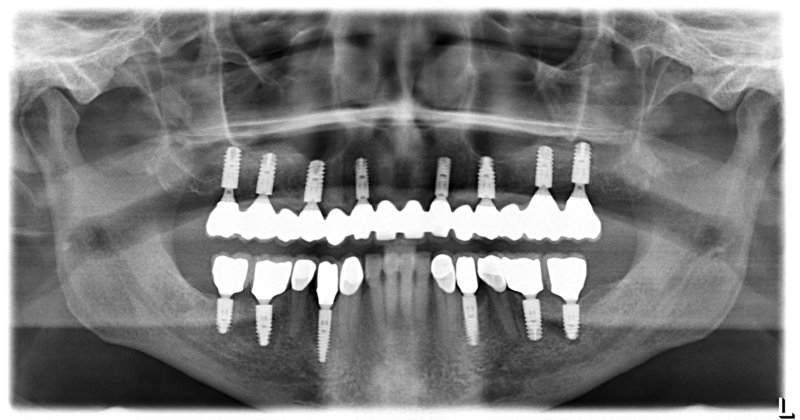

Исследование на рентгене после имплантации зубов

Раздел: Снимки-откровения